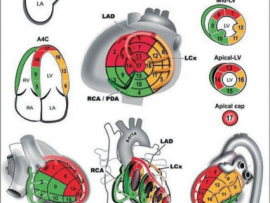

Lee masDifferent Echo views “A4C,A2C,PLAX and PSX” with the corresponding segment and its feeding vessel Mohammed Zidan, MBBCH, M.Sc Cardiology (Cardiology, Echocardiography and interventional Cardilogy Specialist at Al-Azhar..